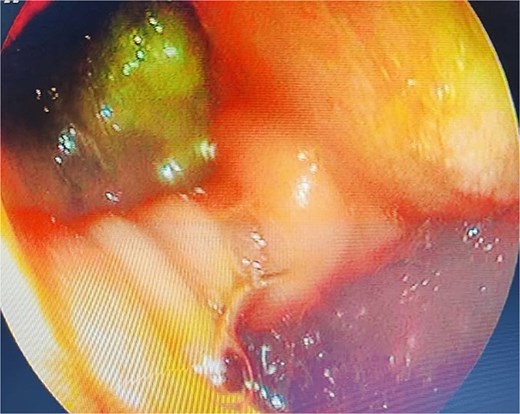

A computed tomography scan confirmed the presence of a duodenal diverticulum (3 cm) in the second part of the duodenum, localized perforation of the gallbladder fundus, and extrahepatic bile duct dilation (Fig. 1). Magnetic resonance cholangiopancreatogram further characterized the findings, revealing biliary stasis secondary to the periampullary diverticulum (Lemmel’s syndrome) without any structural distal obstruction (Fig. 2). Upper gastrointestinal endoscopy excluded periampullary malignancy and confirmed biliary stasis due to the periampullary diverticulum (Fig. 3).

Upper gastrointestinal endoscopy showing duodenal diverticulum.